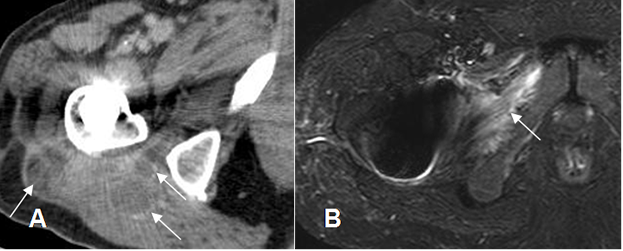

Una complicación frecuente de la artritis séptica, es la formación de abscesos en los tejidos blandos. Los piógenos tienen pared gruesa e irregular y los secundarios a TBC, muestran pared delgada y regular. (17). (Fig 66).

Fig 66. Artritis séptica.

A: TAC axial con contraste. Artritis como complicación de prótesis en la cabeza femoral. Inflamación de tejidos blandos, con incipiente formación de abscesos, cuyos bordes captan el contraste. (Flechas).

B: RM axial en STIR. Extensión de los cambios inflamatorios, hacia el músculo obturador externo.